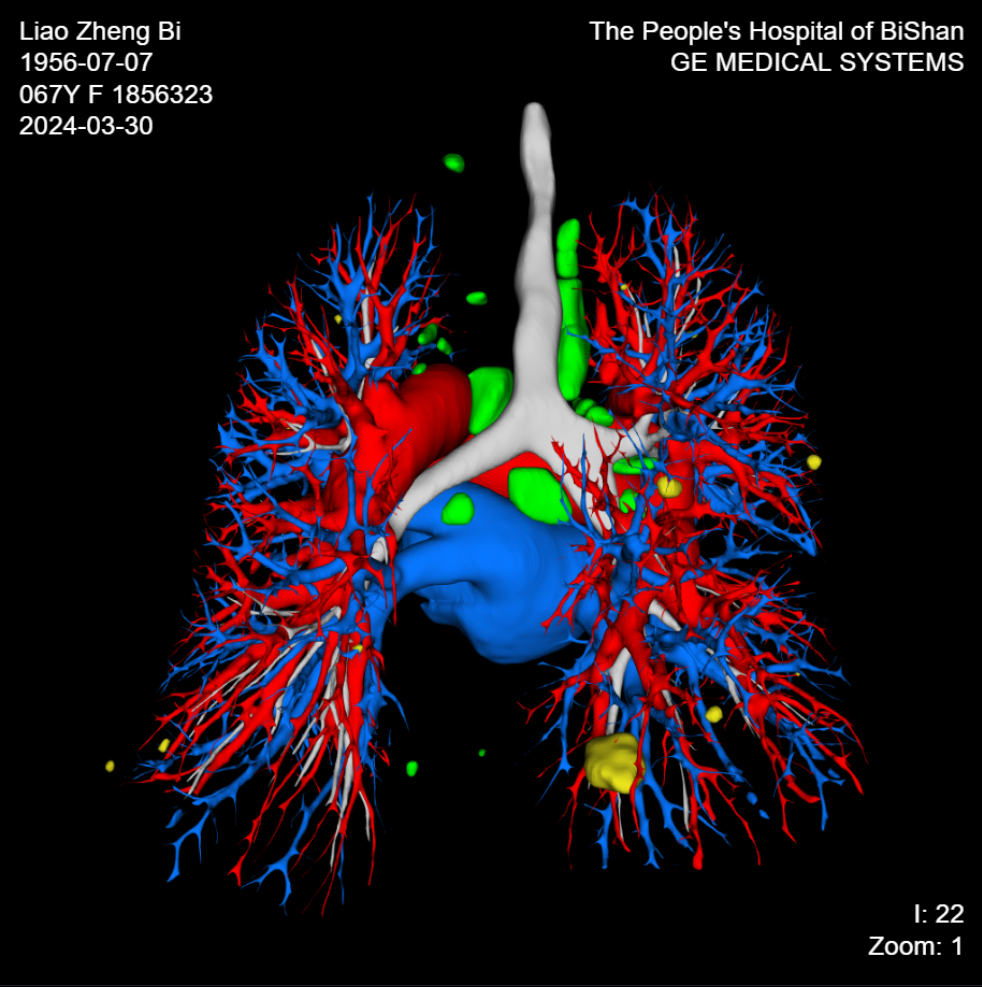

【技術三】肺結節三維可視化重建圖像。可結合原始軸位圖像清晰顯示肺結節與周圍毗鄰關系,尤其是與周圍血管的解剖關系。

【肺結節三維可視化重建圖像】